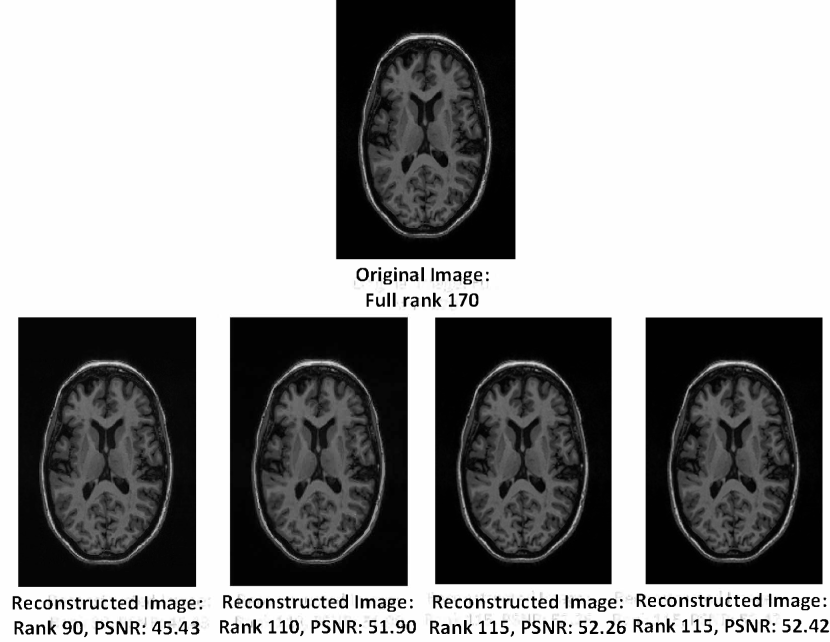

Refer to caption

Figure 2: An example that demonstrates that MR brain images are naturally rank deficient. The low rank images are obtained by zeroing out the smallest singular values (from the SVD). This example reveals that the image has an effective rank in the range 115-120.

Low Rank Prior: It has been demonstrated recently [30, 38, 9, 39] that MR images are naturally rank deficient. For example, Figure 2 shows several low rank images of an MR image reconstructed from partial singular value decomposition (SVD) approximation. We can observe that the recovered image with a rank of 90, which is approximately half of full rank (170) of the image matrix; still exhibits a Peak Signal to Noise Ratio (PSNR) of about 45dB. Further, the reconstruction is visually indistinguishable from the original image. We wish to emphasize that an image being low-rank implies that the effective rank of the matrix is low. For example, it can be observed from Figure 2 that the change in PSNR value in the range of 110-120 rank is relatively negligible compared to that of the PSNR change in the range of 90-110 rank. Hence the effective rank of this particular image can be argued to be in between 115 and 120 which is much smaller than the full rank of 170. Rank of an image captures the global structure of a given image. An effective low-rank implies that the image adheres to some structural properties like near symmetry which can be observed in brain images. Hence, a low-rank constraint is effective in recovering the global structure of a given brain image.